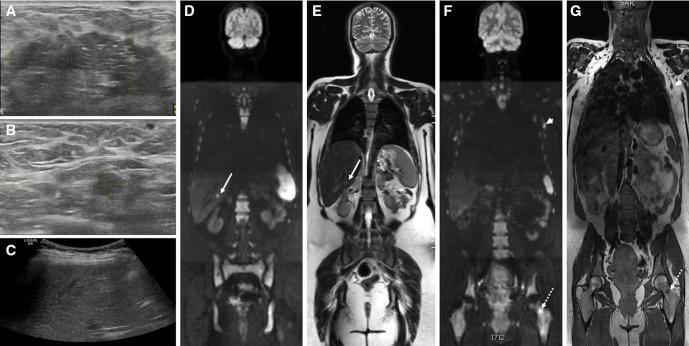

Cancer during pregnancy is increasingly diagnosed due to the trend of delaying pregnancy to a later age and probably also because of increased use of non-invasive prenatal testing for fetal aneuploidy screening with incidental finding of maternal cancer. Pregnant women pose higher challenges in imaging, diagnosis, and staging of cancer. Physiological tissue changes related to pregnancy makes image interpretation more difficult. Moreover, uncertainty about the safety of imaging modalities, fear of (unnecessary) fetal radiation, and lack of standardized imaging protocols may result in underutilization of the necessary imaging tests resulting in suboptimal staging. Due to the absence of radiation exposure, ultrasound and MRI are obvious first-line imaging modalities for detailed locoregional disease assessment. MRI has the added advantage of a more reproducible comprehensive organ or body region assessment, the ability of distant staging through whole-body evaluation, and the combination of anatomical and functional information by diffusion-weighted imaging which obviates the need for a gadolinium-based contrast-agent. Imaging modalities with inherent radiation exposure such as CT and nuclear imaging should only be performed when the maternal benefit outweighs fetal risk. The cumulative radiation exposure should not exceed the fetal radiation threshold of 100 mGy. Imaging should only be performed when necessary for diagnosis and likely to guide or change management. Radiologists play an important role in the multidisciplinary team in order to select the most optimal imaging strategies that balance maternal benefit with fetal risk and that are most likely to guide treatment decisions. Our aim is to provide an overview of possibilities and concerns in current clinical applications and developments in the imaging of patients with cancer during pregnancy.